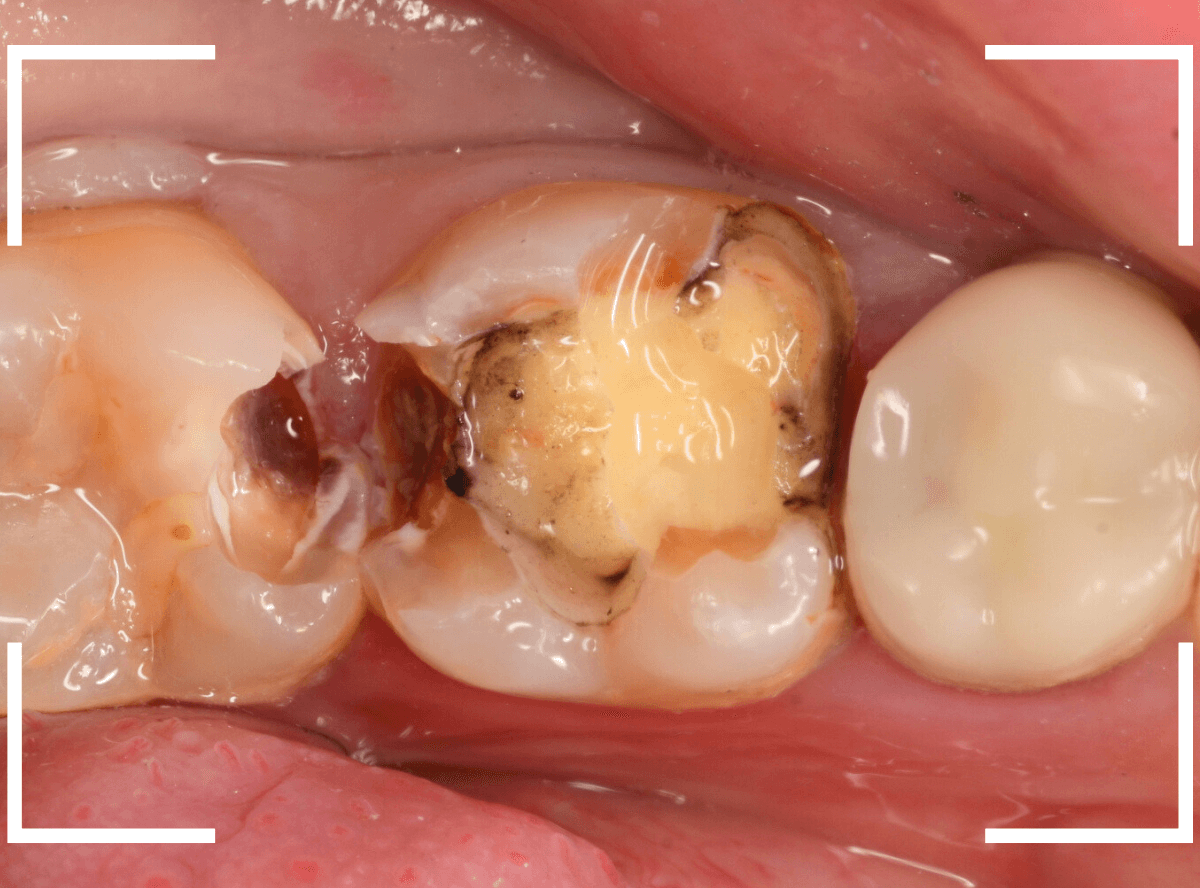

8~9割ほどの虫歯が除去できたかというところですが、

赤く染色されている部分などがまだ虫歯が残っている部分です。

エキスカベーターを使ってほぼ全ての虫歯を除去したところです。

幸い、神経寸前で虫歯はとどまっていましたが、お薬を詰めて、しばらく経過観察します。